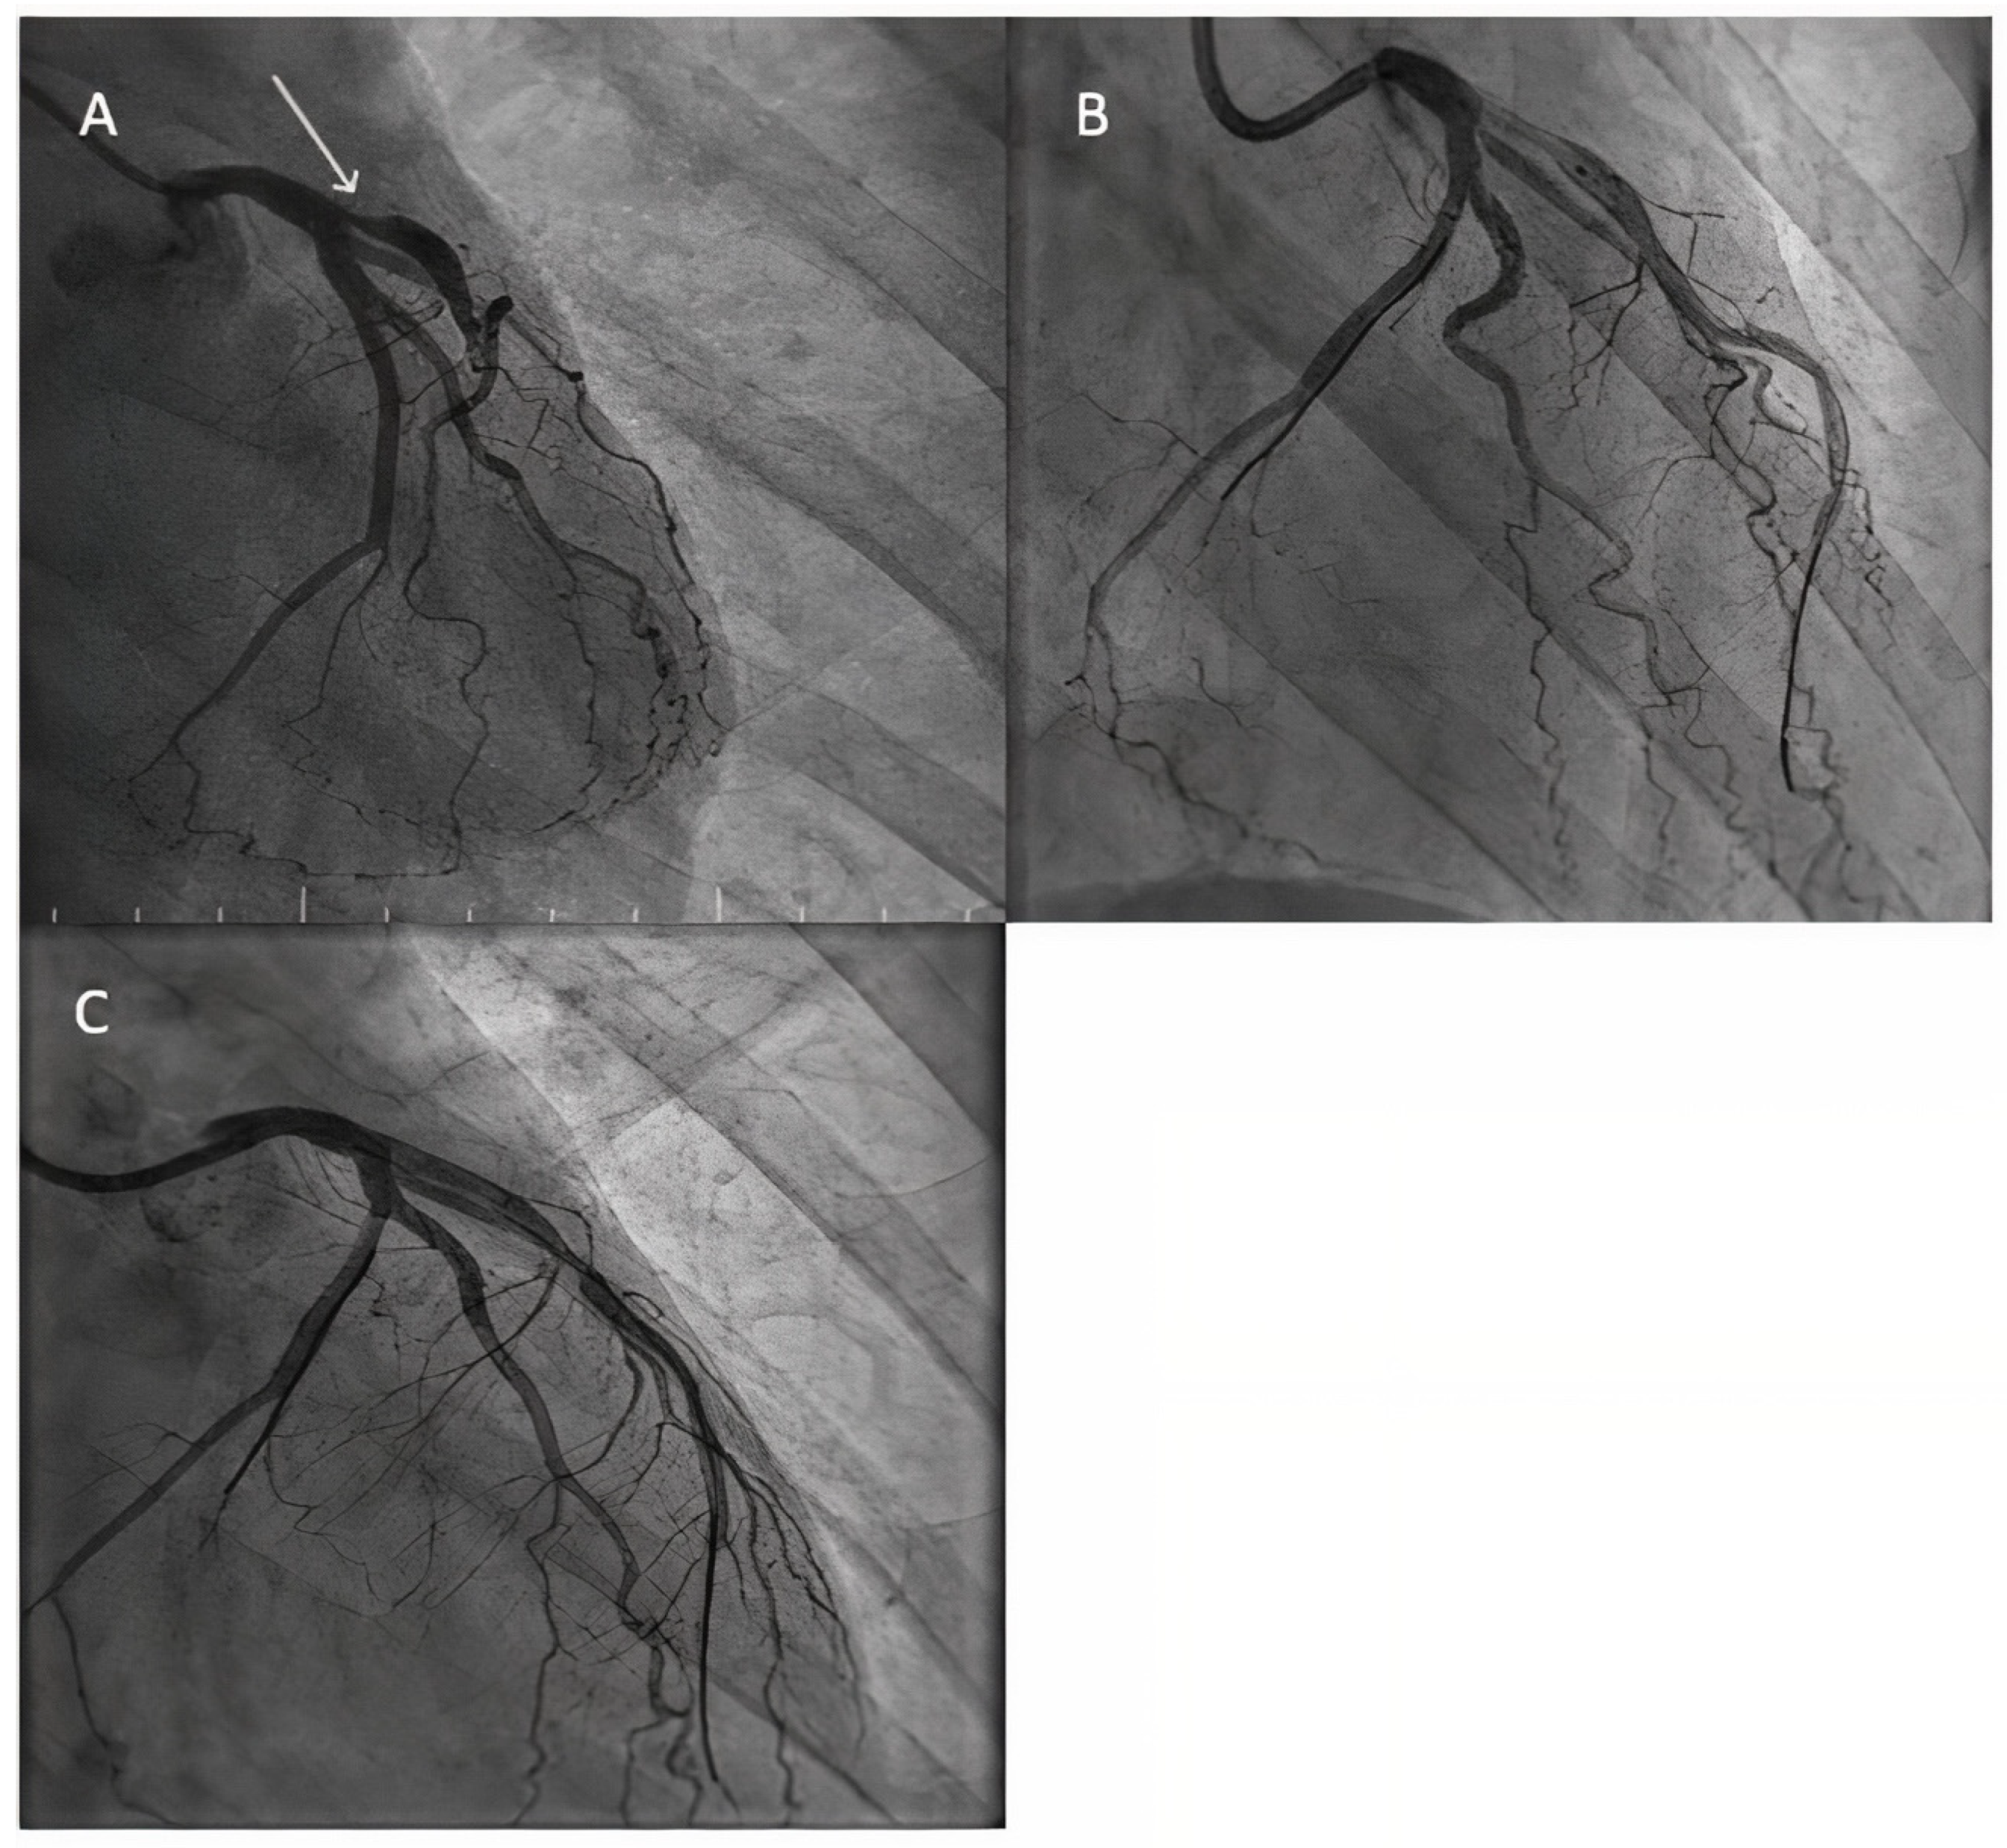

- Lazar, F.L.; Prvulović, Đ.; Onea, H.L.; Cortese, B. The role of drug-coated balloons for coronary bifurcation management: Results from the prospective EASTBOURNE-BIF study. Minerva Cardiol. Angiol. 2024, 72, 346–354. [Google Scholar] [CrossRef]